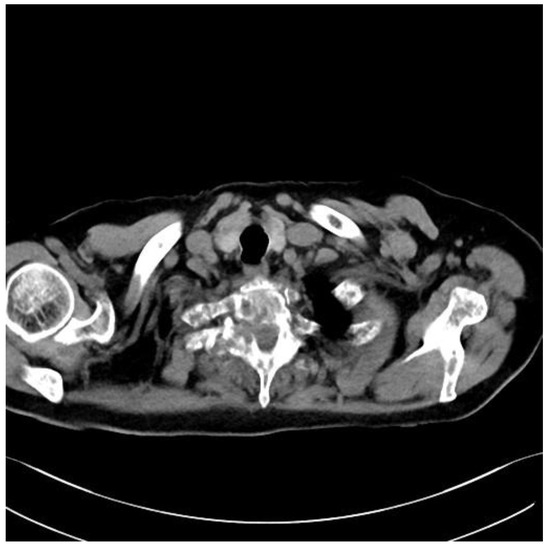

Fully Endoscopic Spine Separation Surgery in Metastatic Disease—Case Series, Technical Notes, and Preliminary Findings